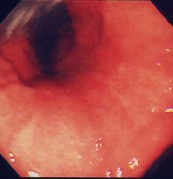

胃潰瘍:

心窩部痛、食欲不振、黒色便を訴えて来院。内視鏡検査を施行すると類円形の活動期の潰瘍を認めました。良性の潰瘍で内服治療で十分に治癒します。現在、潰瘍の原因はピロリ菌であるされ、潰瘍の治療としてピロリ菌をやっつける(除菌)ことが認められています。潰瘍を何度も繰り返している方は、是非除菌療法を考慮してください。